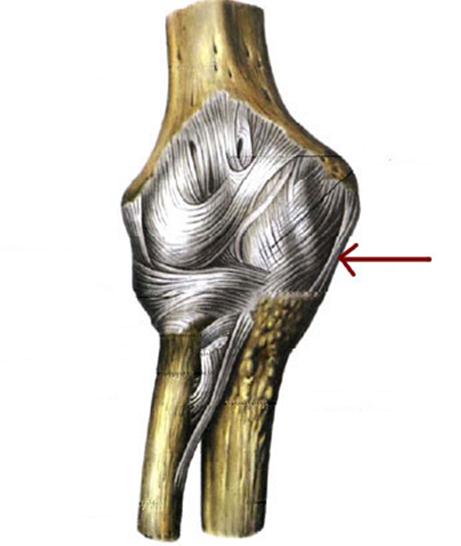

S: Стрелка указывает на... плечевой кости.

+:tuberculum majus

-:tuberculum minus

-:epicondylus medialis

-:troсhlea

-:capitulum